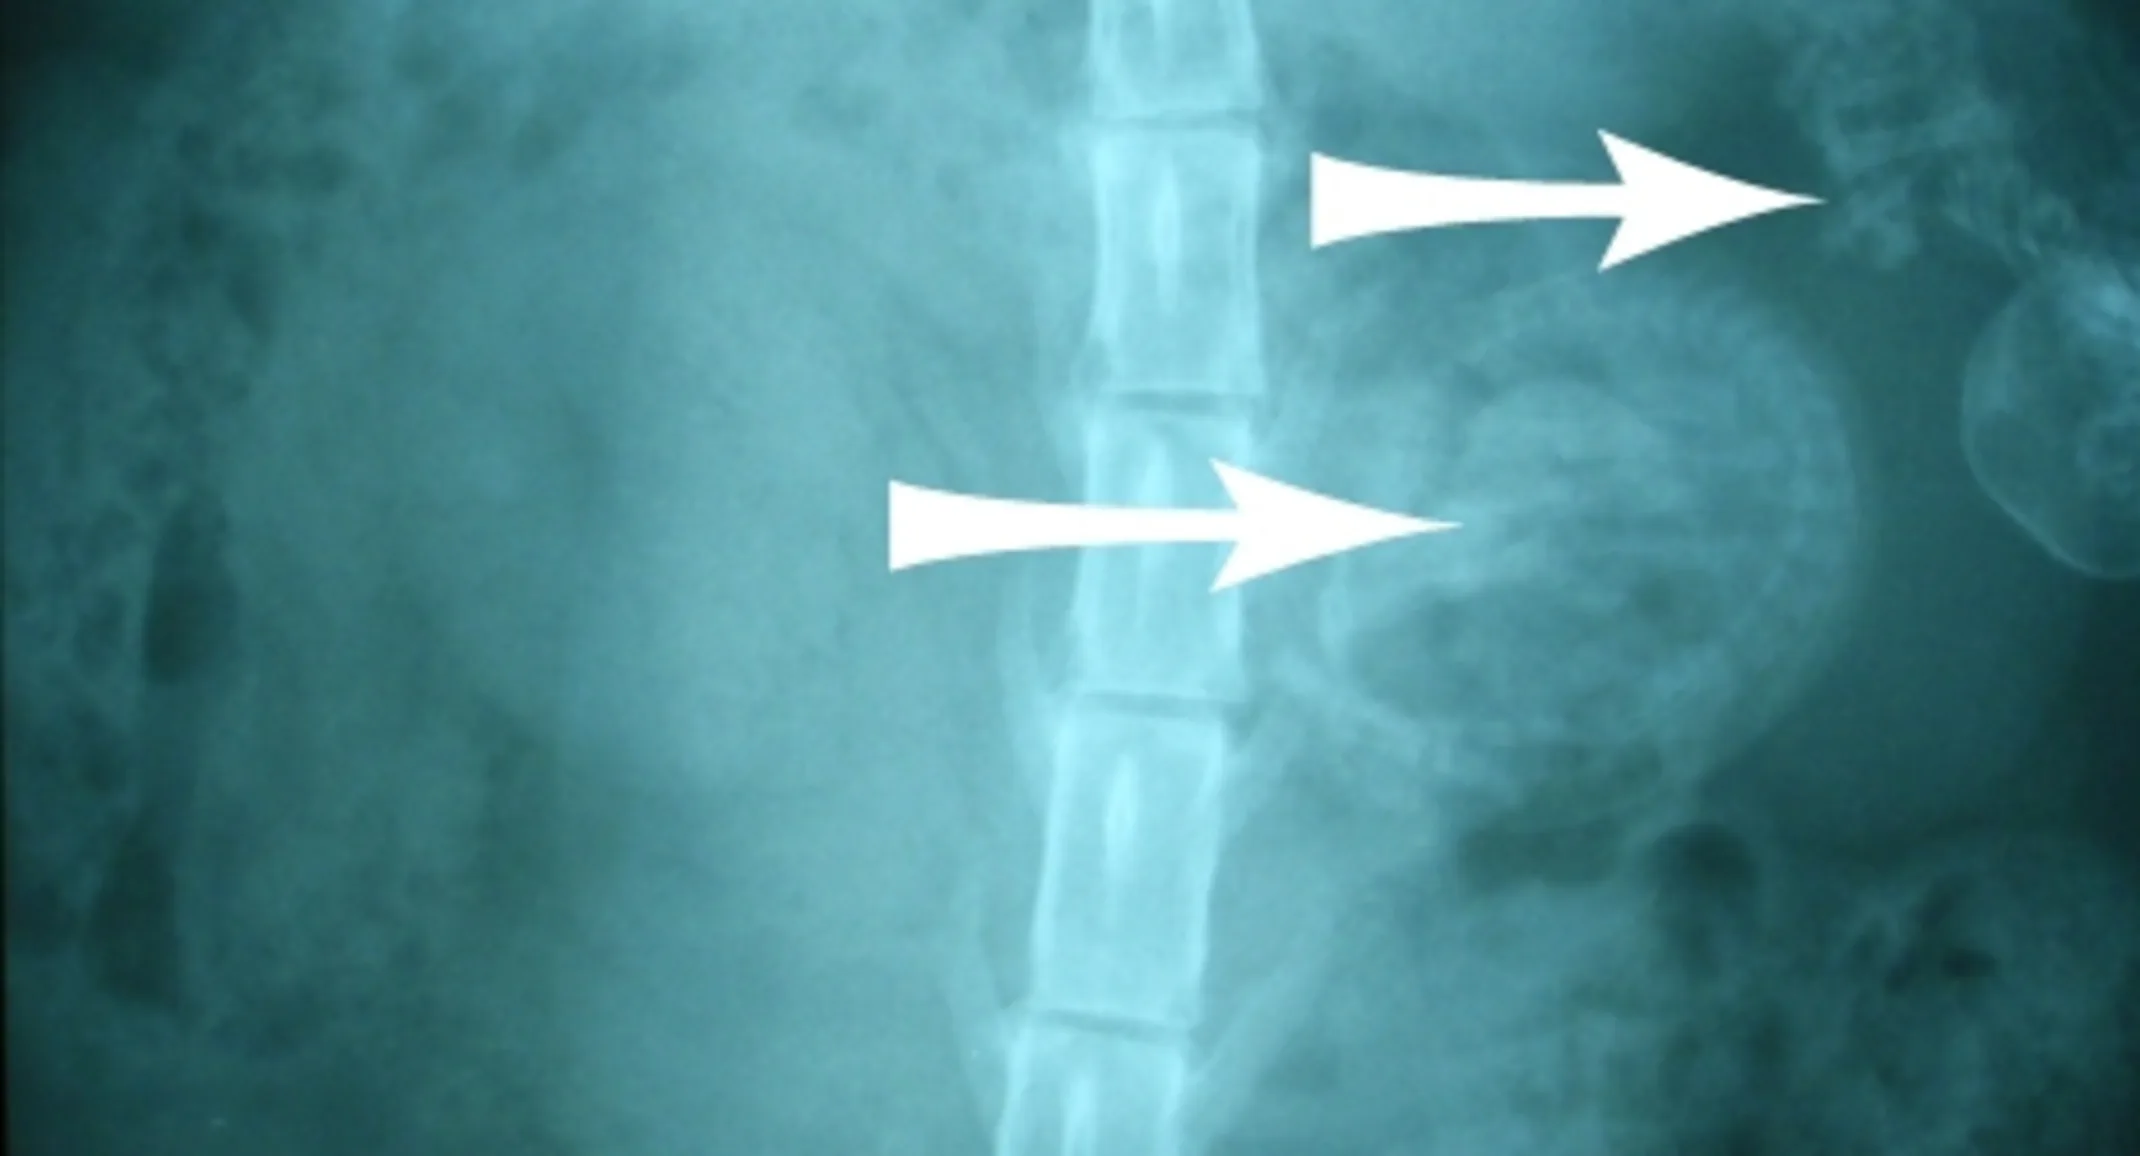

Surprisingly, we saw two fetuses in her abdomen. I confirmed with the veterinarian that performed the spay procedure, at another veterinary clinic, that Lena had both of her ovaries and her uterus removed. The abdominal radiograph (x-ray) shown above does identify 2 kittens in the abdomen (white arrows pointing to each one) and we could see the kitten’s vertebrae and skulls on the radiograph.